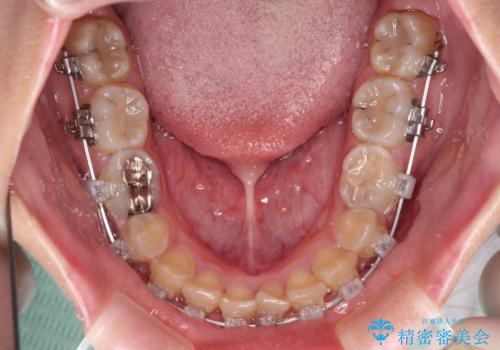

- クリアブラケット

- 1年2ヶ月

犬歯は歯根が太くて長いため、クロスバイトを改善するのは大変であることが多いですが、比較的スムーズに改善することができました。

インビザラインであったら、もっと期間はかかっていたような印象です。